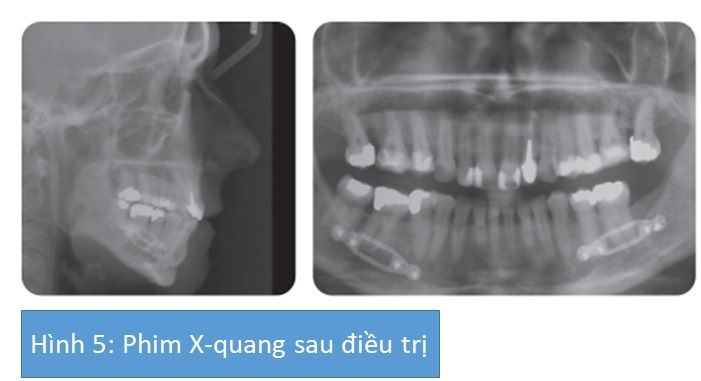

Nhận xét kết quả cuối cùng

Có sự cải thiện gương mặt nhìn nghiêng, mặc dù có dư 1 chút da cùng nhọng-cằm do kết quả của việc đưa hàm dưới ra trước và phẫu thuật thu nhỏ cằm. Độ cắn chìa và đường giữa đã được sửa lại.